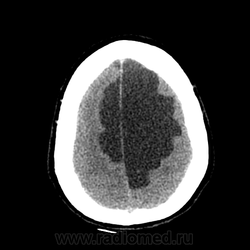

Мало что понимаю в КТ, но как то на ОНМК не тянет. Не могу понять почему сигнал (извините привыкла все сигналами оценивать) от образования какой же что и от желудочка?!

На объем как то тоже не похоже. , сигнал равномерный и такой же как и от ликвора. Если расценивать как последствия ОНМК так это как должно было " рвануть" да еще и с поражением желудочков - не пациент бы вряд ли выжел. Как же сложно в этом к/т ! Не знаю может это глупо, но у меня пока впечатление о врожденной патологии мозга. А с контрастом не делали ? Или вам и так все понятно, Сергей Николаевич , тогда поделитесь мыслями пожалуйста.

Создается впечатление о нехватке/недостатке мозгового вещества.

Действительно любопытно! Только сканов мало. Пока мысль о кисте полости межжелудочковой перегородки. Нет ли там где препятствия или изолированная киста?))

Эпидермоидная киста?

Я бы может сказала что здесь агенезия мозолистого тела. Как мне не хватает МРТ данных (. Агенезия ? Перегородки. Сергей Николаевич подскажите возраст пожалуйста. Здесь должна быть выраженная неврологическая клиника. Расскажите побольше о пациенте.

Эпидермоид может расти, при ТИА может быть случайной находкой. А тут ещё окклюзионная гидроцефалия.

Может, это две межполушарные арахноидальные кисты?

Больному около 55 лет, клинику дает не сколько само образование, а компрессия структур мозга, базально вообще беда (отчасти видно компреммию некоторых базальных цистерн мозга). Сразу скажу насчет эпидермоидной кисты - ДВИ не будет :)

Однозначно киста, значит, осталось выяснить какая, холестеатома или арахноидальная?